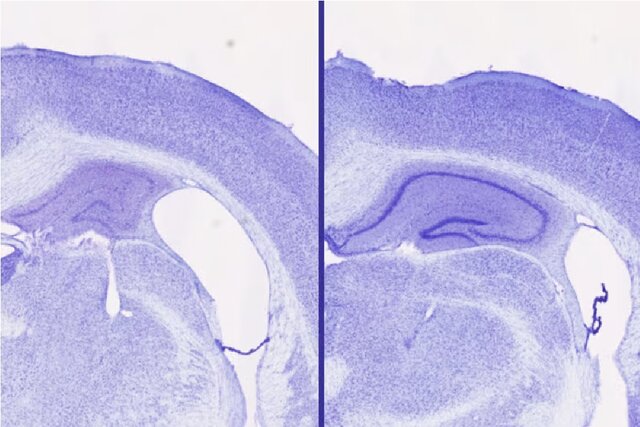

موشهای مصرفکننده «لمبورکسانت» 30 تا 40 درصد حجم مغز بیشتری در هیپوکامپ (ناحیهای حیاتی برای عملکرد شناختی سالم) نسبت به حیواناتی که زولپیدم مصرف میکردند، داشتند. حتی اگر هر دو گروه تقریباً به یک میزان خواب داشتند. از دست دادن حجم مغز، نشانهای از تخریب عصبی است.